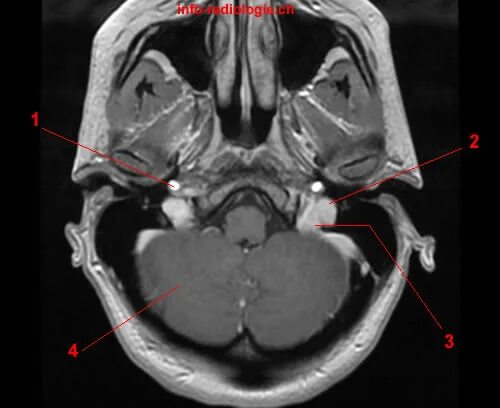

Асимметрия поперечных сигмовидных синусов s d